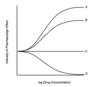

Which letter corresponds with the region where dead space is the greatest?

A

B

C

D

D

Dead space is ventilation without perfusion and shunt is perfusion without ventilation.

The graph examines the V/Q relationship in the entire lung.

Point C marks where ventilation and perfusion are equally matched.

Point D marks the region where ventilation is greater than perfusion; dead space is increased here.

Points A and B mark where perfusion exceeds ventilation; shunt is increased here.